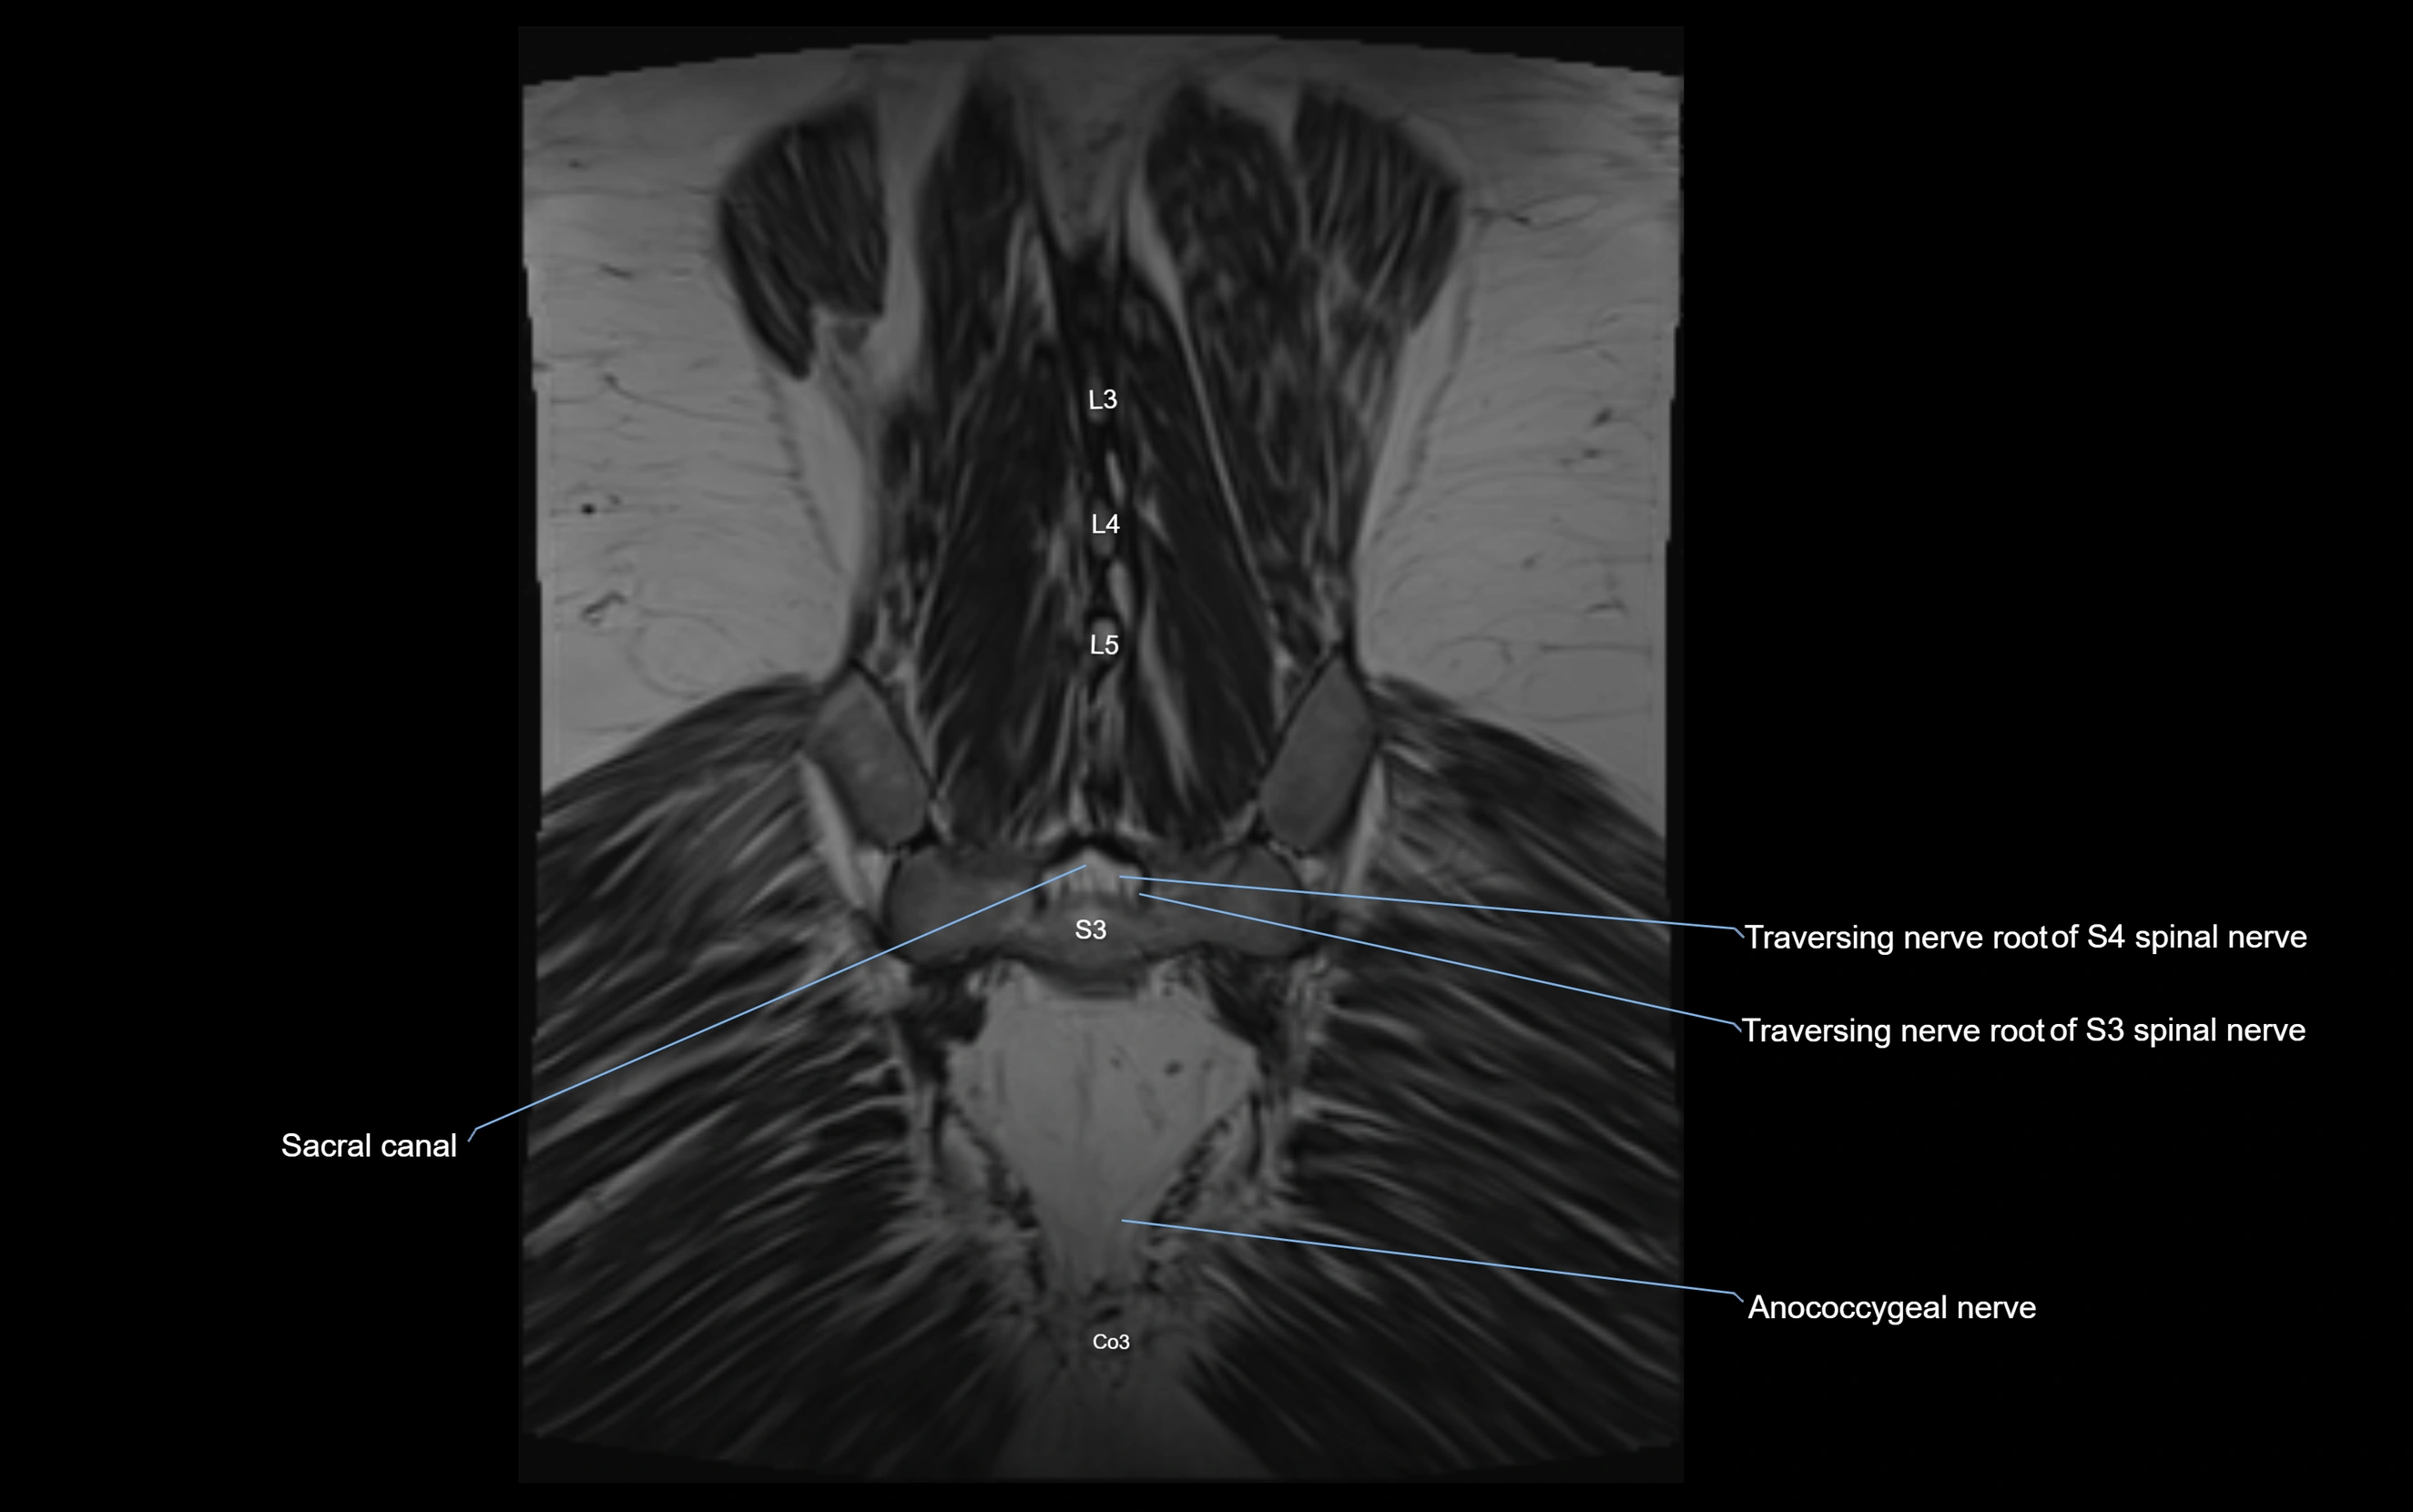

Anococcygeal nerve

The anococcygeal nerve is a small sensory nerve derived from the coccygeal plexus, which itself is formed by the ventral rami of S4, S5, and the coccygeal nerve (Co1). Although tiny, this nerve plays an important role in supplying the skin of the coccyx and the area between the anus and coccyx. It passes through the sacrotuberous ligament and runs in the midline behind the coccyx.

MRI image

image